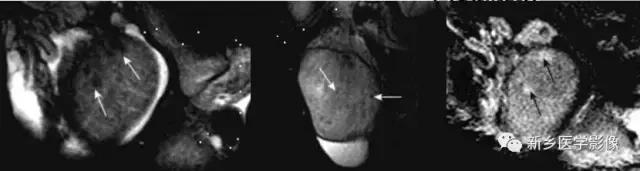

MR:*丸睾**炎T2WI不仅要低信号,增强扫描不均匀强化,合并鞘膜腔积液

MR:精原细胞瘤各信号偏低、均匀、散在,恶性病变,信号可不均;非精原细胞瘤信号不均

MR

急性扭转的*丸睾**体积增大,可见出血